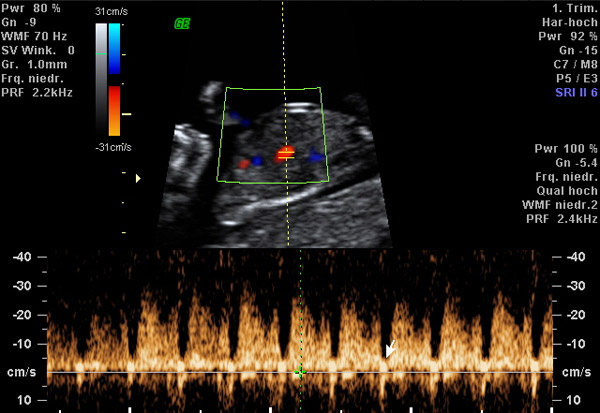

Spezielles Ultraschallverfahren zur Messung von Blutströmen in kindlichen

und mütterlichen Gefäßen. Dadurch kann die Befindlichkeit des Föten,

die Versorgungsqualität des Mutterkuchens und die Neigung zur Gestose

(früher als Schwangerschaftsvergiftung bezeichnet) untersucht und

vorhersehend überprüft werden. Diese Untersuchung ist fester Bestandteil

der sonographischen Feindiagnostik und sollte auch bei Risikoschwangerschaften

ggf. regelmäßig durchgeführt werden. Typische Indikationen sind: